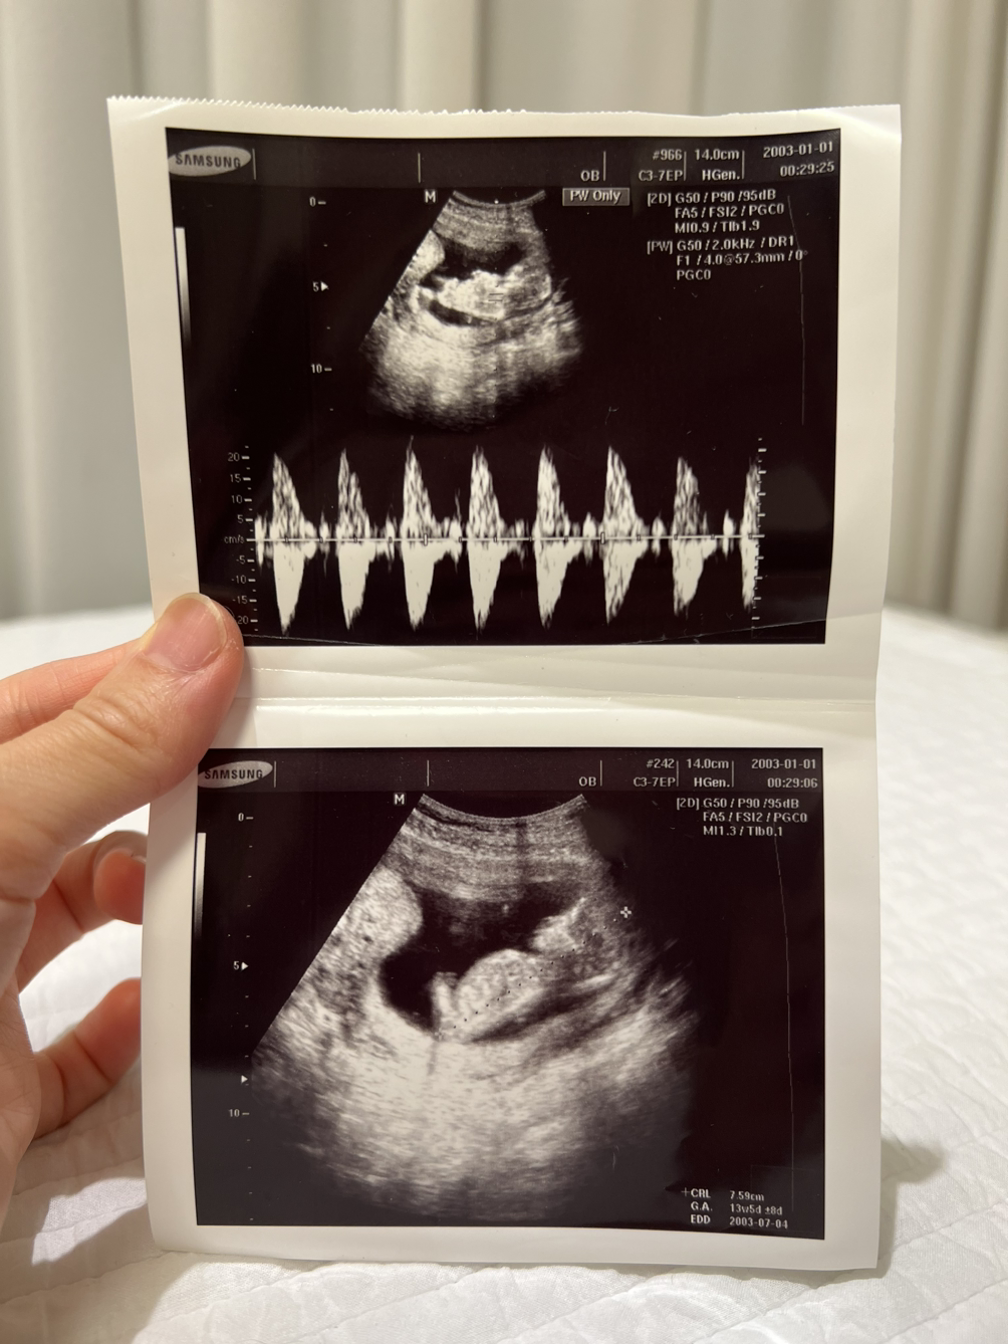

데스크에 가서 하혈이 있었던 시간과 양, 배의 통증 등 증상을 간략히 이야기하고 진료실로 들어갔고, 마침 담당 선생님이 오늘 당직이었다며 곧이어 들어와 초음파검사를 포함해 몇 가지 진찰을 해주셨다.

- 많이 놀라셨죠? 출혈이 있을 수 있는 이유는.. 피고임이 있거나 경부에 상처가 있거나 하는 등의 이유가 있는데 환자분은 지금 그 두 가지 경우는 다 아니요. 출혈이 생기는 이유는 워낙 다양해서요.. 현재 진료로는 이유를 알 수가 없네요. 우선 초음파로 보기에는 아기도 잘 있고.. 심장 소리도 이상 없어요.

초음파 사진을 손에 들고 진료실을 나왔더니 남편 얼굴이 사색이 되어있었다.

손에 들고 있던 초음파 사진을 하임이에게 건네주었다.

- 여기가 머리, 배, 다리인가 보다. 아기 모양처럼 보이지?

남편이 옆에서 초음파 사진을 가리키며 알려주자 혀를 내밀며 눈이 동그래진다.